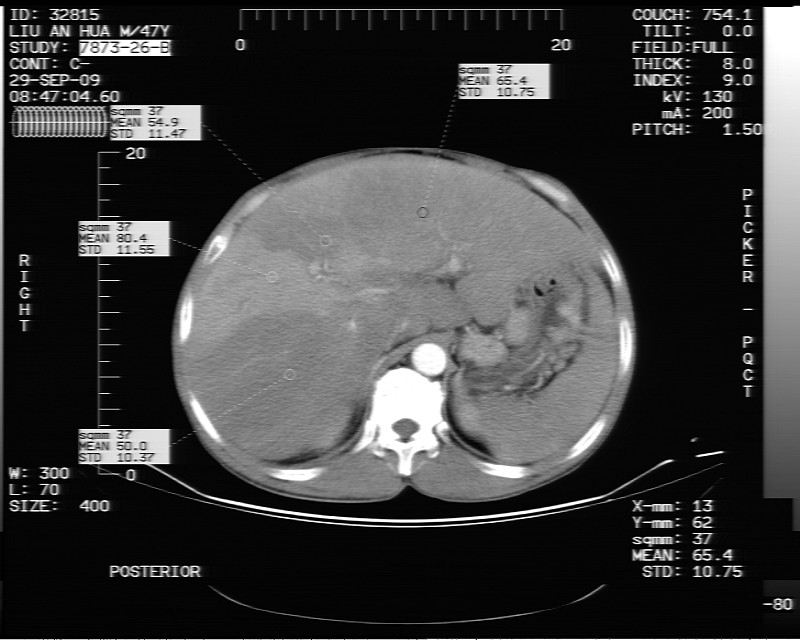

平扫示:

动态增强示:

支持脂肪肝【无占位性,高低密度区同期强化,平扫与强化的密度成比例】

不均匀性脂肪肝。肝脏体积稍大,不除外合并肝功能损害。

1.脂肪肝;

2.右肾结石。

1、不均匀脂肪肝;2、布加氏综合症(肝脏肿大,门脉纤细,下腔海绵状变性,肠系膜上静脉显著扩张)。